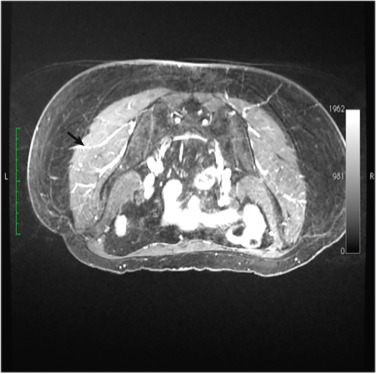

Magnetic resonance angiograms (MRA) are a mainstay of our patients’ preoperative work-up ( Fig. 5.2 ). The angiograms allow a qualitative evaluation of perforator location, course, and caliber. Hence, they are integral to the presurgical planning. Our radiologists use a coordinate system with reference points such as the midine and the gluteal fold to describe the perforators’ location as they exit the muscle. Each perforator coordinate is measured in its vertical and horizontal position with respect to these landmarks. Perforator selection is multifactorial, which is why each case must be tailored according to the imaging and patient body habitus. A large vessel diameter, pedicle of sufficient length for insetting, central location of the vessel on the flap, or a pattern of arborization that suggests perfusion of the tissue to be transferred are all considered favorable for the choice of the pedicle to be used. Use of the angiogram in conjunction with a pencil Doppler facilitates the most accurate identification of the perforators prior to the surgery. This method is particularly helpful in designing the skin paddle that will capture the perforators.